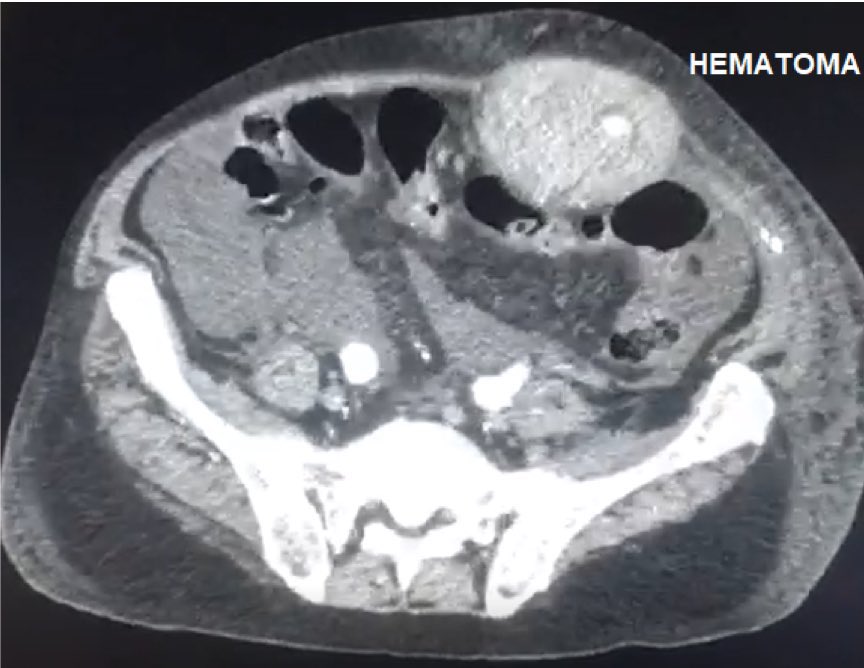

Embolization of the inferior epigastric artery in a huge abdominal wall hematoma caused by paracentesis in a patient with liver cirrhosis.

@seleno_glauber We were able to do the infrarenal clamping, it was a stable paciente non rupted.

@AndrePoci Did you achieve a infrarenal approach at first attempt or begun with a supraceliac clamping?

PS: I’ve never seen such a left kidney displacement. Amazing.